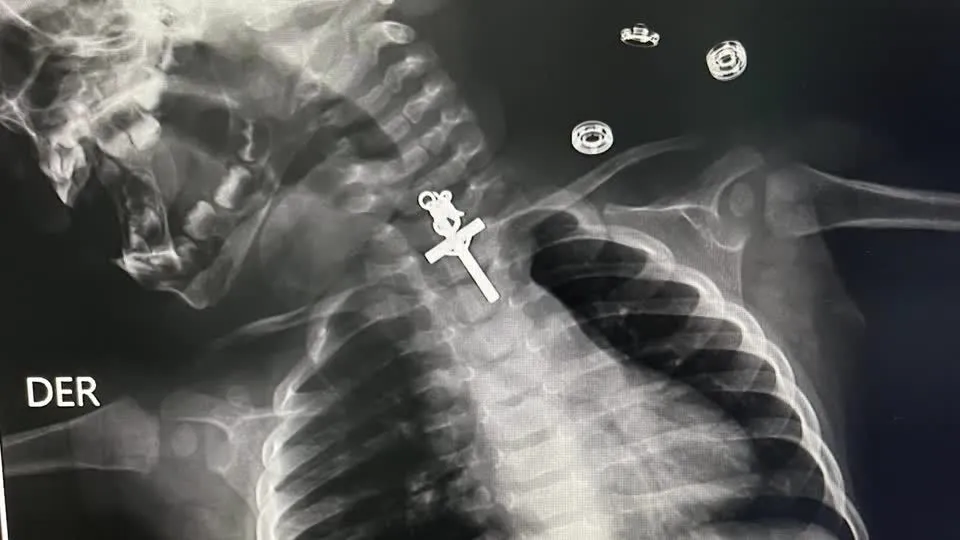

Imagens de raio-X mostraram um crucifixo alojado no esôfago de um bebê de 10 meses. A criança foi atendida no Hospital Victor Lazarte Echegaray, em La Libertad, no Peru, onde foi submetida a uma endoscopia para retirada do corpo estranho.

O artefato foi removido com sucesso pela equipe médica no sábado (11). “O procedimento foi muito complicado porque era um crucifixo e estava alojado no terço superior do esôfago. Mesmo quando tentamos retirá-lo inicialmente, não conseguimos, estava preso, então tentamos várias vezes até que consegui retirar o corpo estranho”, disse o médico responsável, Luis Esteves Cabanillas.